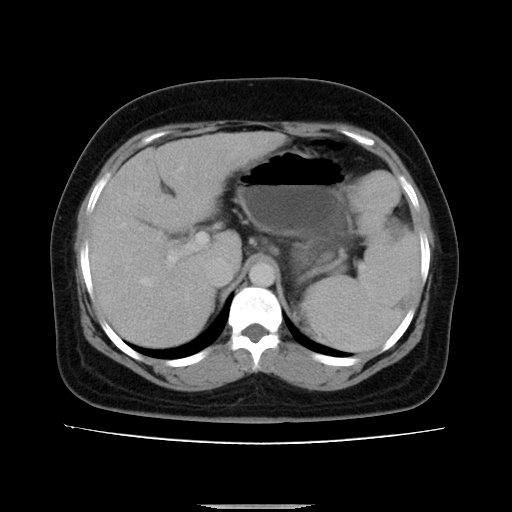

标题: CT14225:女性46岁。当地B超示肝内占位,来我院作CT检查。请 [打印本页]

标题: CT14225:女性46岁。当地B超示肝内占位,来我院作CT检查。请

右叶肝癌灶;慢性胆囊炎,不除外占位;;副脾可能性

肝内结节强化特点符合原发性肝癌表现,脾脏改变考虑为增大及先天发育所致。

肝硬化,脾亢。

符合肝癌表现,脾脏大(肝硬化?)

非常典型,肝ca,脾脏先天性发育异常,脾大

此患者虽然符合快进的特点,却不符合快出的特点,因为门脉期几乎是等密度,不符合肝癌的增强表现,所以我考虑肝局灶性结节增生可能性大

肝内结节强化特点符合原发性肝癌表现。脾大。

快进快出,符合肝癌表现。脾脏改变考虑为增大及先天发育所致。